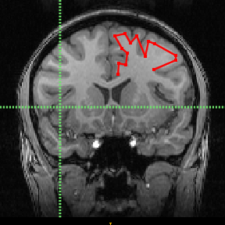

Isotropic segmentation pipeline for MTL subregions from multi-modality 3T MRI